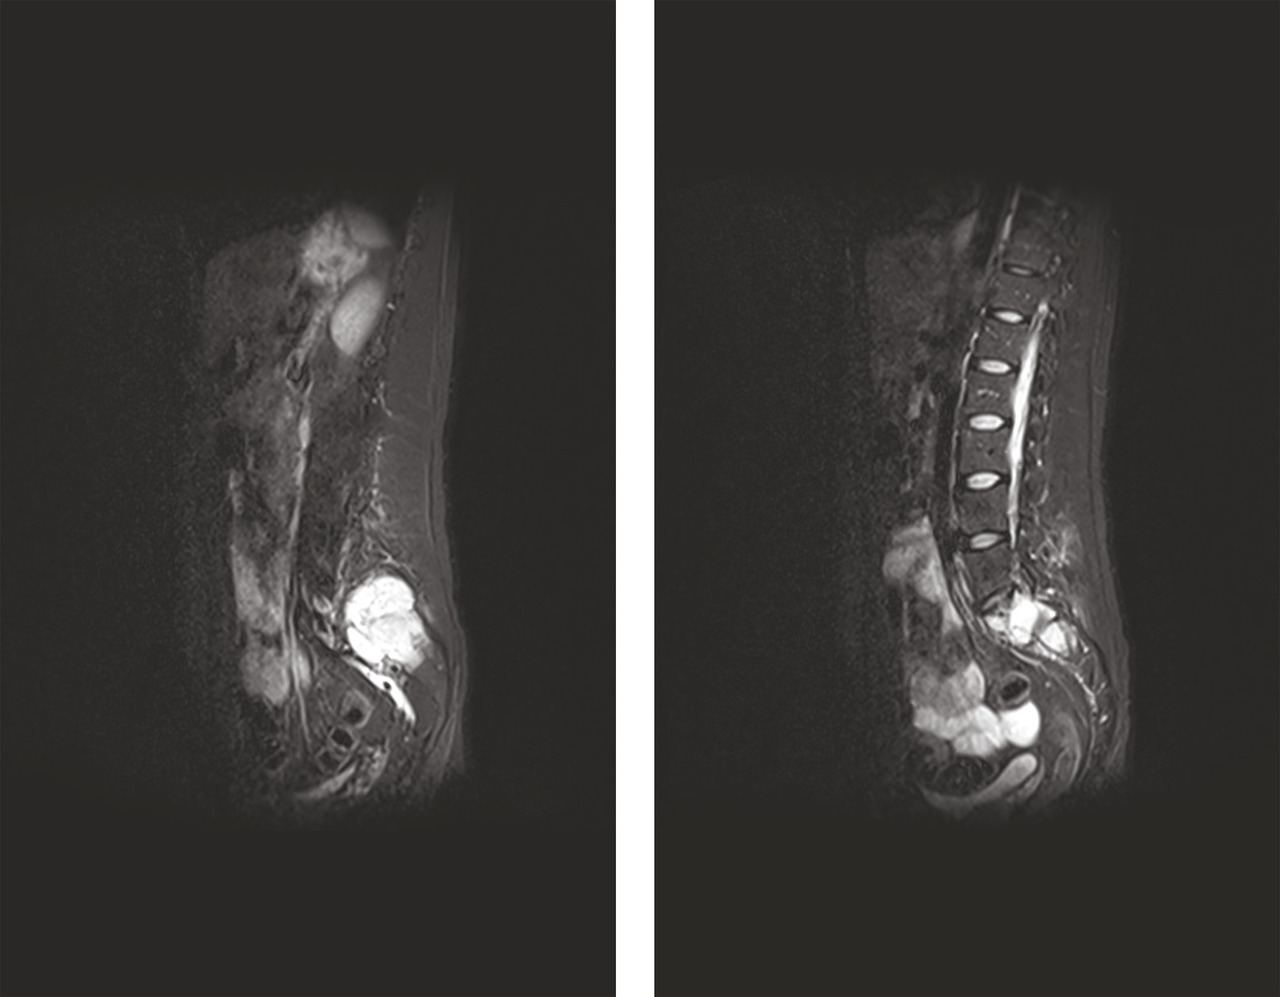

Le bilan biologique n’a pas montré de syndrome inflammatoire (hémogramme, protéine C réactive [CRP] et vitesse de sédimentation [VS] normaux). Les radiographies standard du bassin et du rachis lombaire, de même que l’échographie des hanches, étaient sans particularité. Mais la radiographie pulmonaire de face a mis en évidence une opacité médiastinale parahilaire droite se raccordant en pente douce avec le médiastin ainsi qu’une interface nette avec le poumon, évoquant une tumeur médiastinale (fig. 1).

L’IRM couplée du rachis et du bassin a révélé la présence de trois lésions tissulaires vertébrales (en T3, T4 et T5) et d’une lésion plus volumineuse de l’aileron sacré gauche infiltrant le premier trou sacré gauche (fig. 3). L’hypothèse de lésions métastatiques a alors été privilégiée.